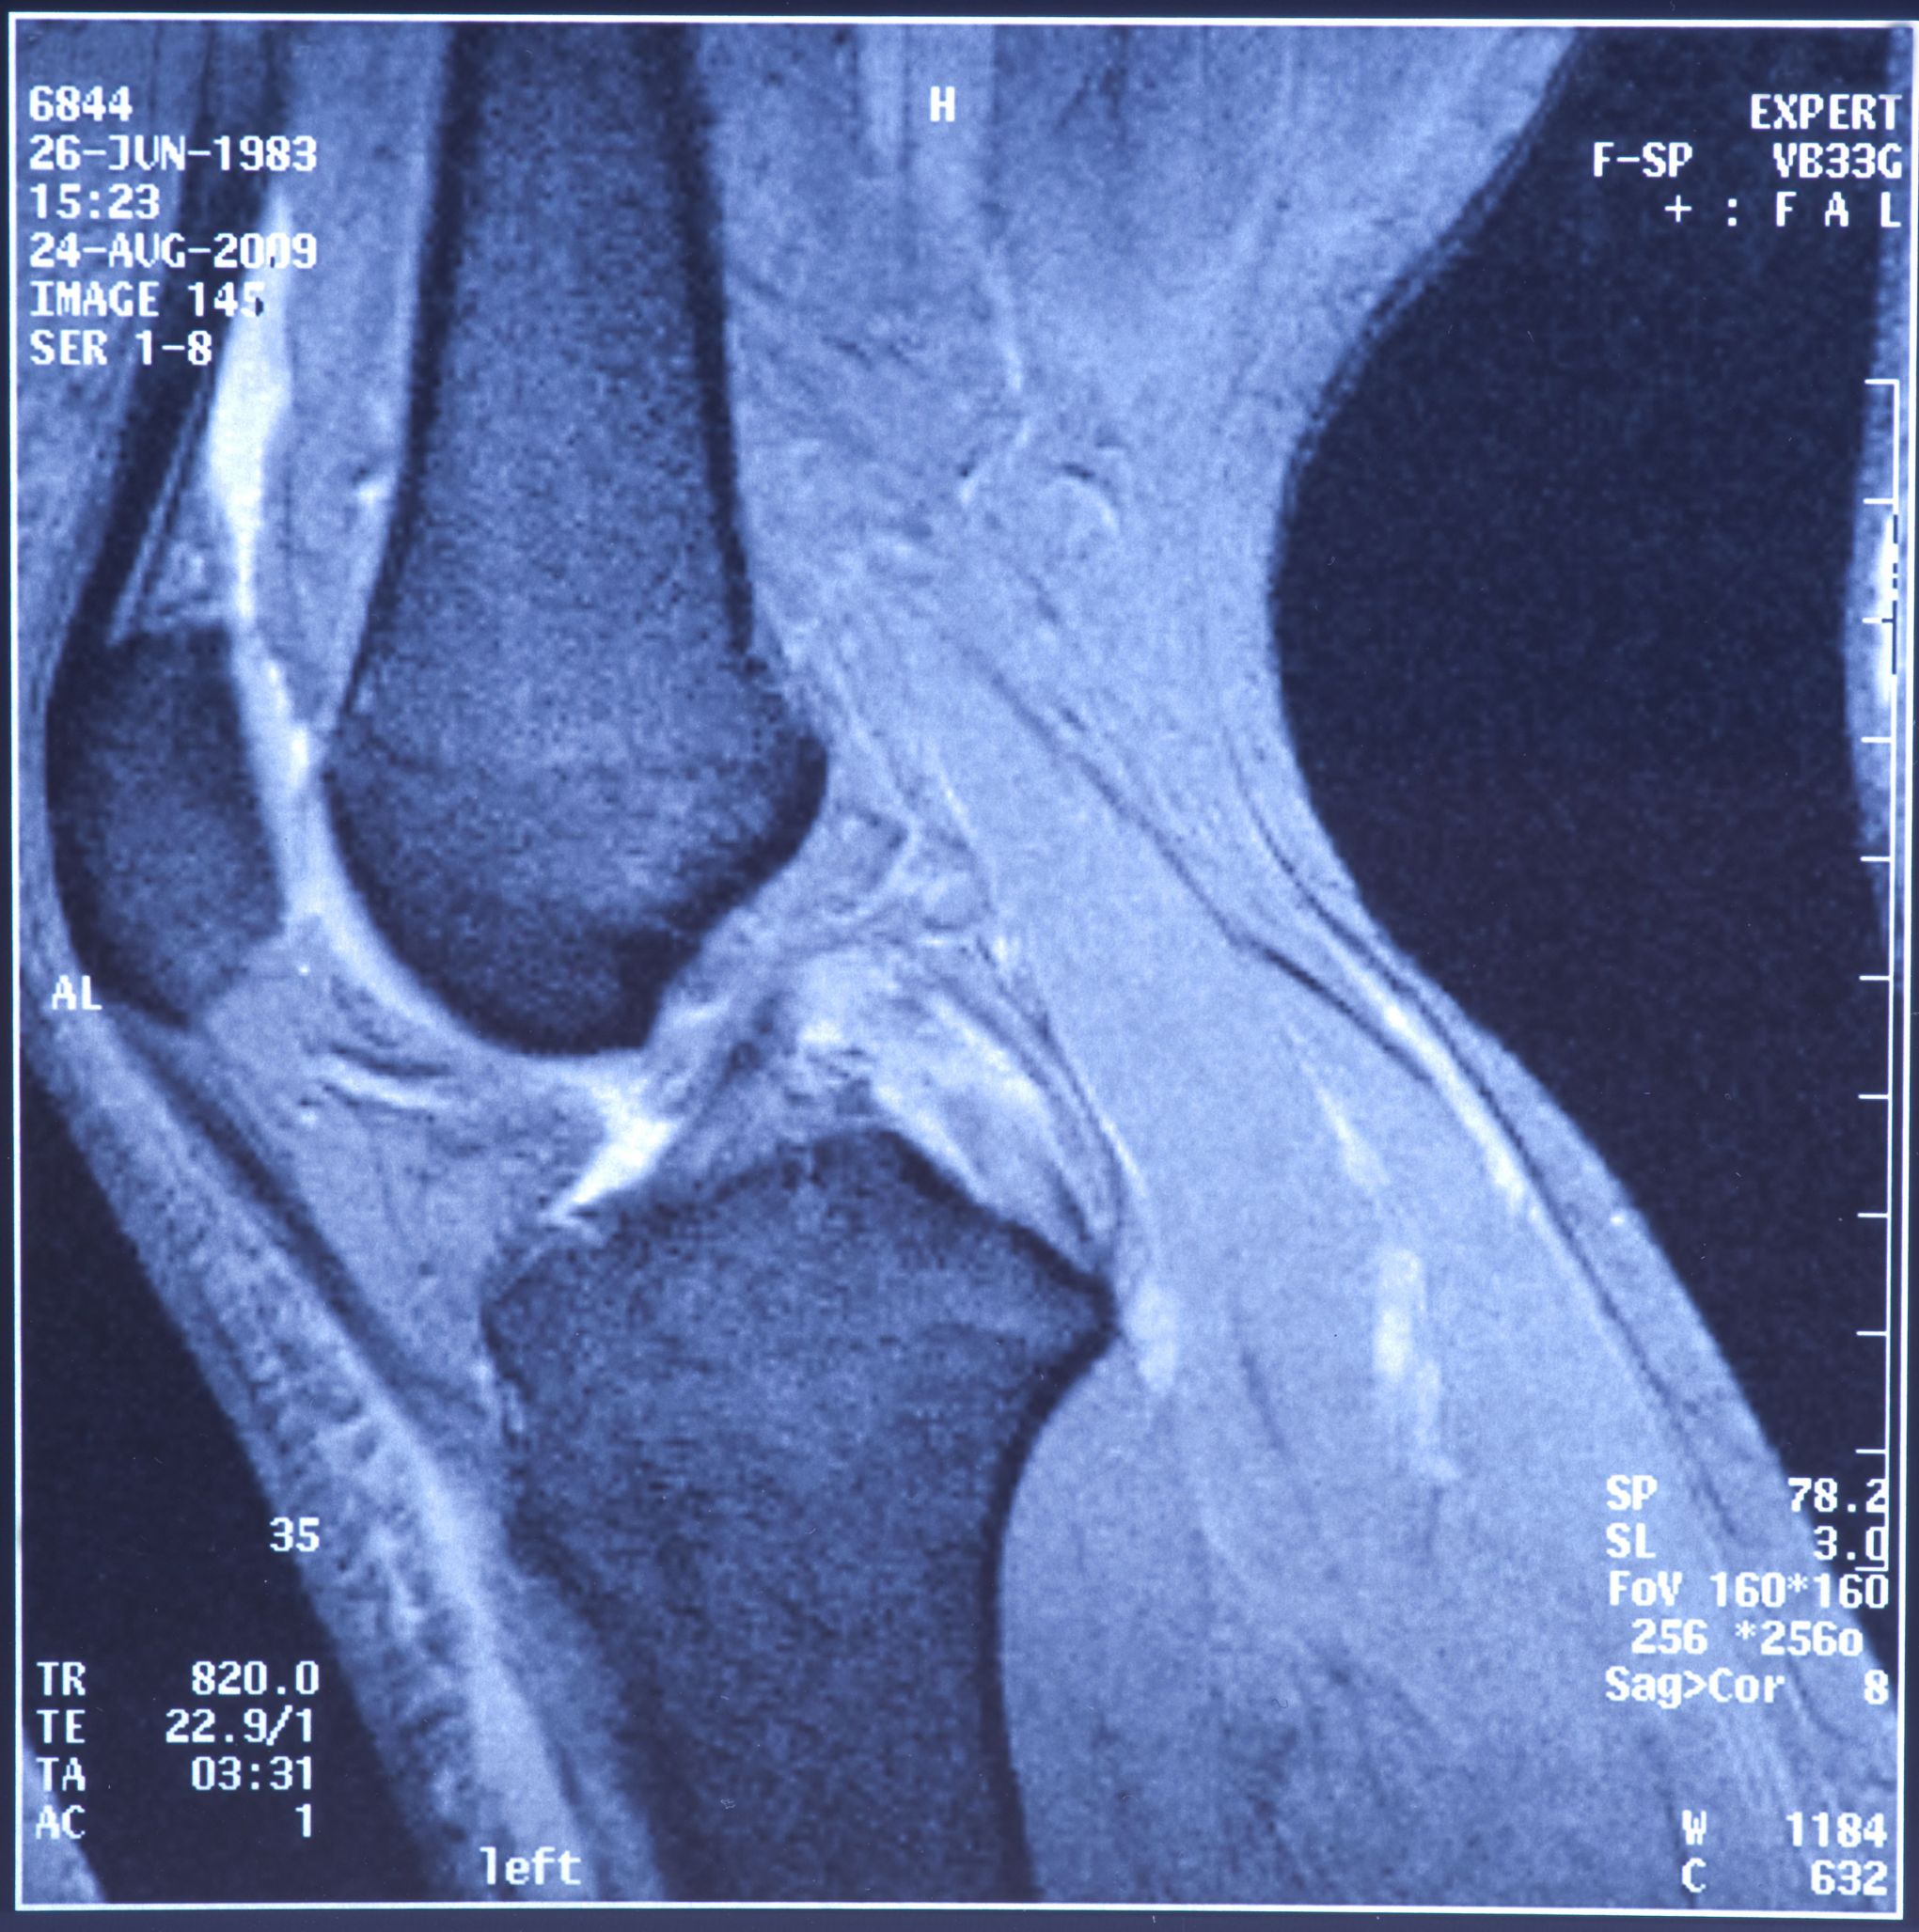

Patellofemoral syndrome Dr. Michael Serhal